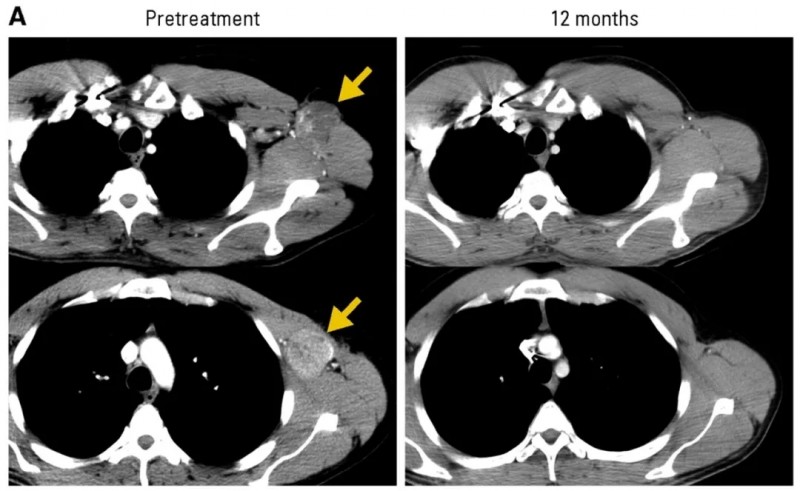

1、5号转移性黑色素瘤患者:在治疗后多发性复发性腋窝淋巴结完全消退,目前完全缓解(CR)已维持20个月(详见下图A)。

▲图源“J Clin Oncol ”,版权归原作者所有,如无意中侵犯了知识产权,请联系我们删除